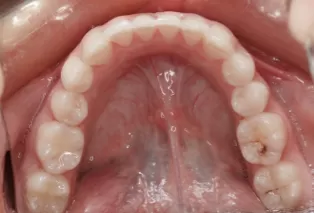

Photos intra-orales après traitement